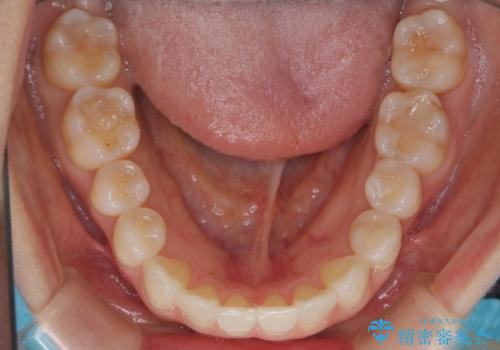

- インビザラインで非抜歯治療を行いました。IPRと拡大をし、叢生、咬合をきれいにしました。

主訴であったかみ合わせを正しい位置に動かし、バランスよくかめるようになりました。矯正治療終了後にメタルインレーをセラミックインレーに替えました。